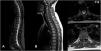

Nervous system involvement is uncommon in granulomatosis with polyangiitis (GPA), a systemic autoimmune disease with episodes of necrotizing vasculitis. It is usually due to the compressive effect of dural or epidural masses. Spinal hemorrhagic presentation is exceptional. A 41-year-old woman diagnosed with GPA presented with three episodes of acute spinal subdural hematoma separated by eight years and ten months, respectively. The symptomatic debut was pain and paresis in all episodes. On all occasions, a lesion compatible with acute spinal subdural hematoma was diagnosed by magnetic resonance imaging (MRI). All episodes were treated conservatively with corticosteroids and immunosuppressants. The patient presented complete neurological recovery in the first two episodes. A mild residual left lower limb paresis remains after the last one. Follow-up MRI was performed after all episodes, and no focal intraspinal lesions were detected. Spinal subdural hemorrhage is a form of manifestation of GPA, either as a debut or in the course of the disease. We describe the third confirmed case of spontaneous spinal hemorrhage secondary to GPA published in the literature and the first with recurrence. Given the extraordinary response to immunosuppressive therapy, a high level of clinical suspicion is necessary to establish treatment as early as possible.

Presentamos un caso en una paciente diagnosticada de granulomatosis con poliangeitis (GPA) que presentó en dos ocasiones separadas por un lapso de 8 años, hematoma subdural agudo espinal con diferentes niveles de afectación en cada uno de los episodios. Se añade una revisión de la literatura. Una mujer de 48 años diagnosticada de GPA, presentó tres episodios de hematoma subdural espinal agudo; separados por un período de tiempo en primer lugar de 8 años y en segundo lugar de 10 meses. Clínicamente, las tres veces se manifestaron con dolor y paresia. En todas las ocasiones, se diagnosticó mediante Resonancia Magnética Nuclear (RMN) la presencia de una lesión compatible con hematoma subdural espinal agudo. Todos los episodios se trataron de forma conservadora con corticoesteroides y Rituximab. La paciente presentó recuperación neurológica completa en los dos primeros episodios. En relación al último; presenta una paresia leve en miembro inferior izquierdo. En todos los episodios se realizó control por RMN y no se detectaron alteraciones intraespinales. La hemorragia subdural espinal es una posible forma de manifestación de la GPA, bien como debut o en el curso de la enfermedad. Es necesario un alto nivel de sospecha clínica para establecer el tratamiento de la forma más precoz posible. Presenta una respuesta extraordinaria a la terapia inmunosupresora. Es posible una recuperación completa a través del tratamiento conservador. Recomendamos un abordaje combinado.